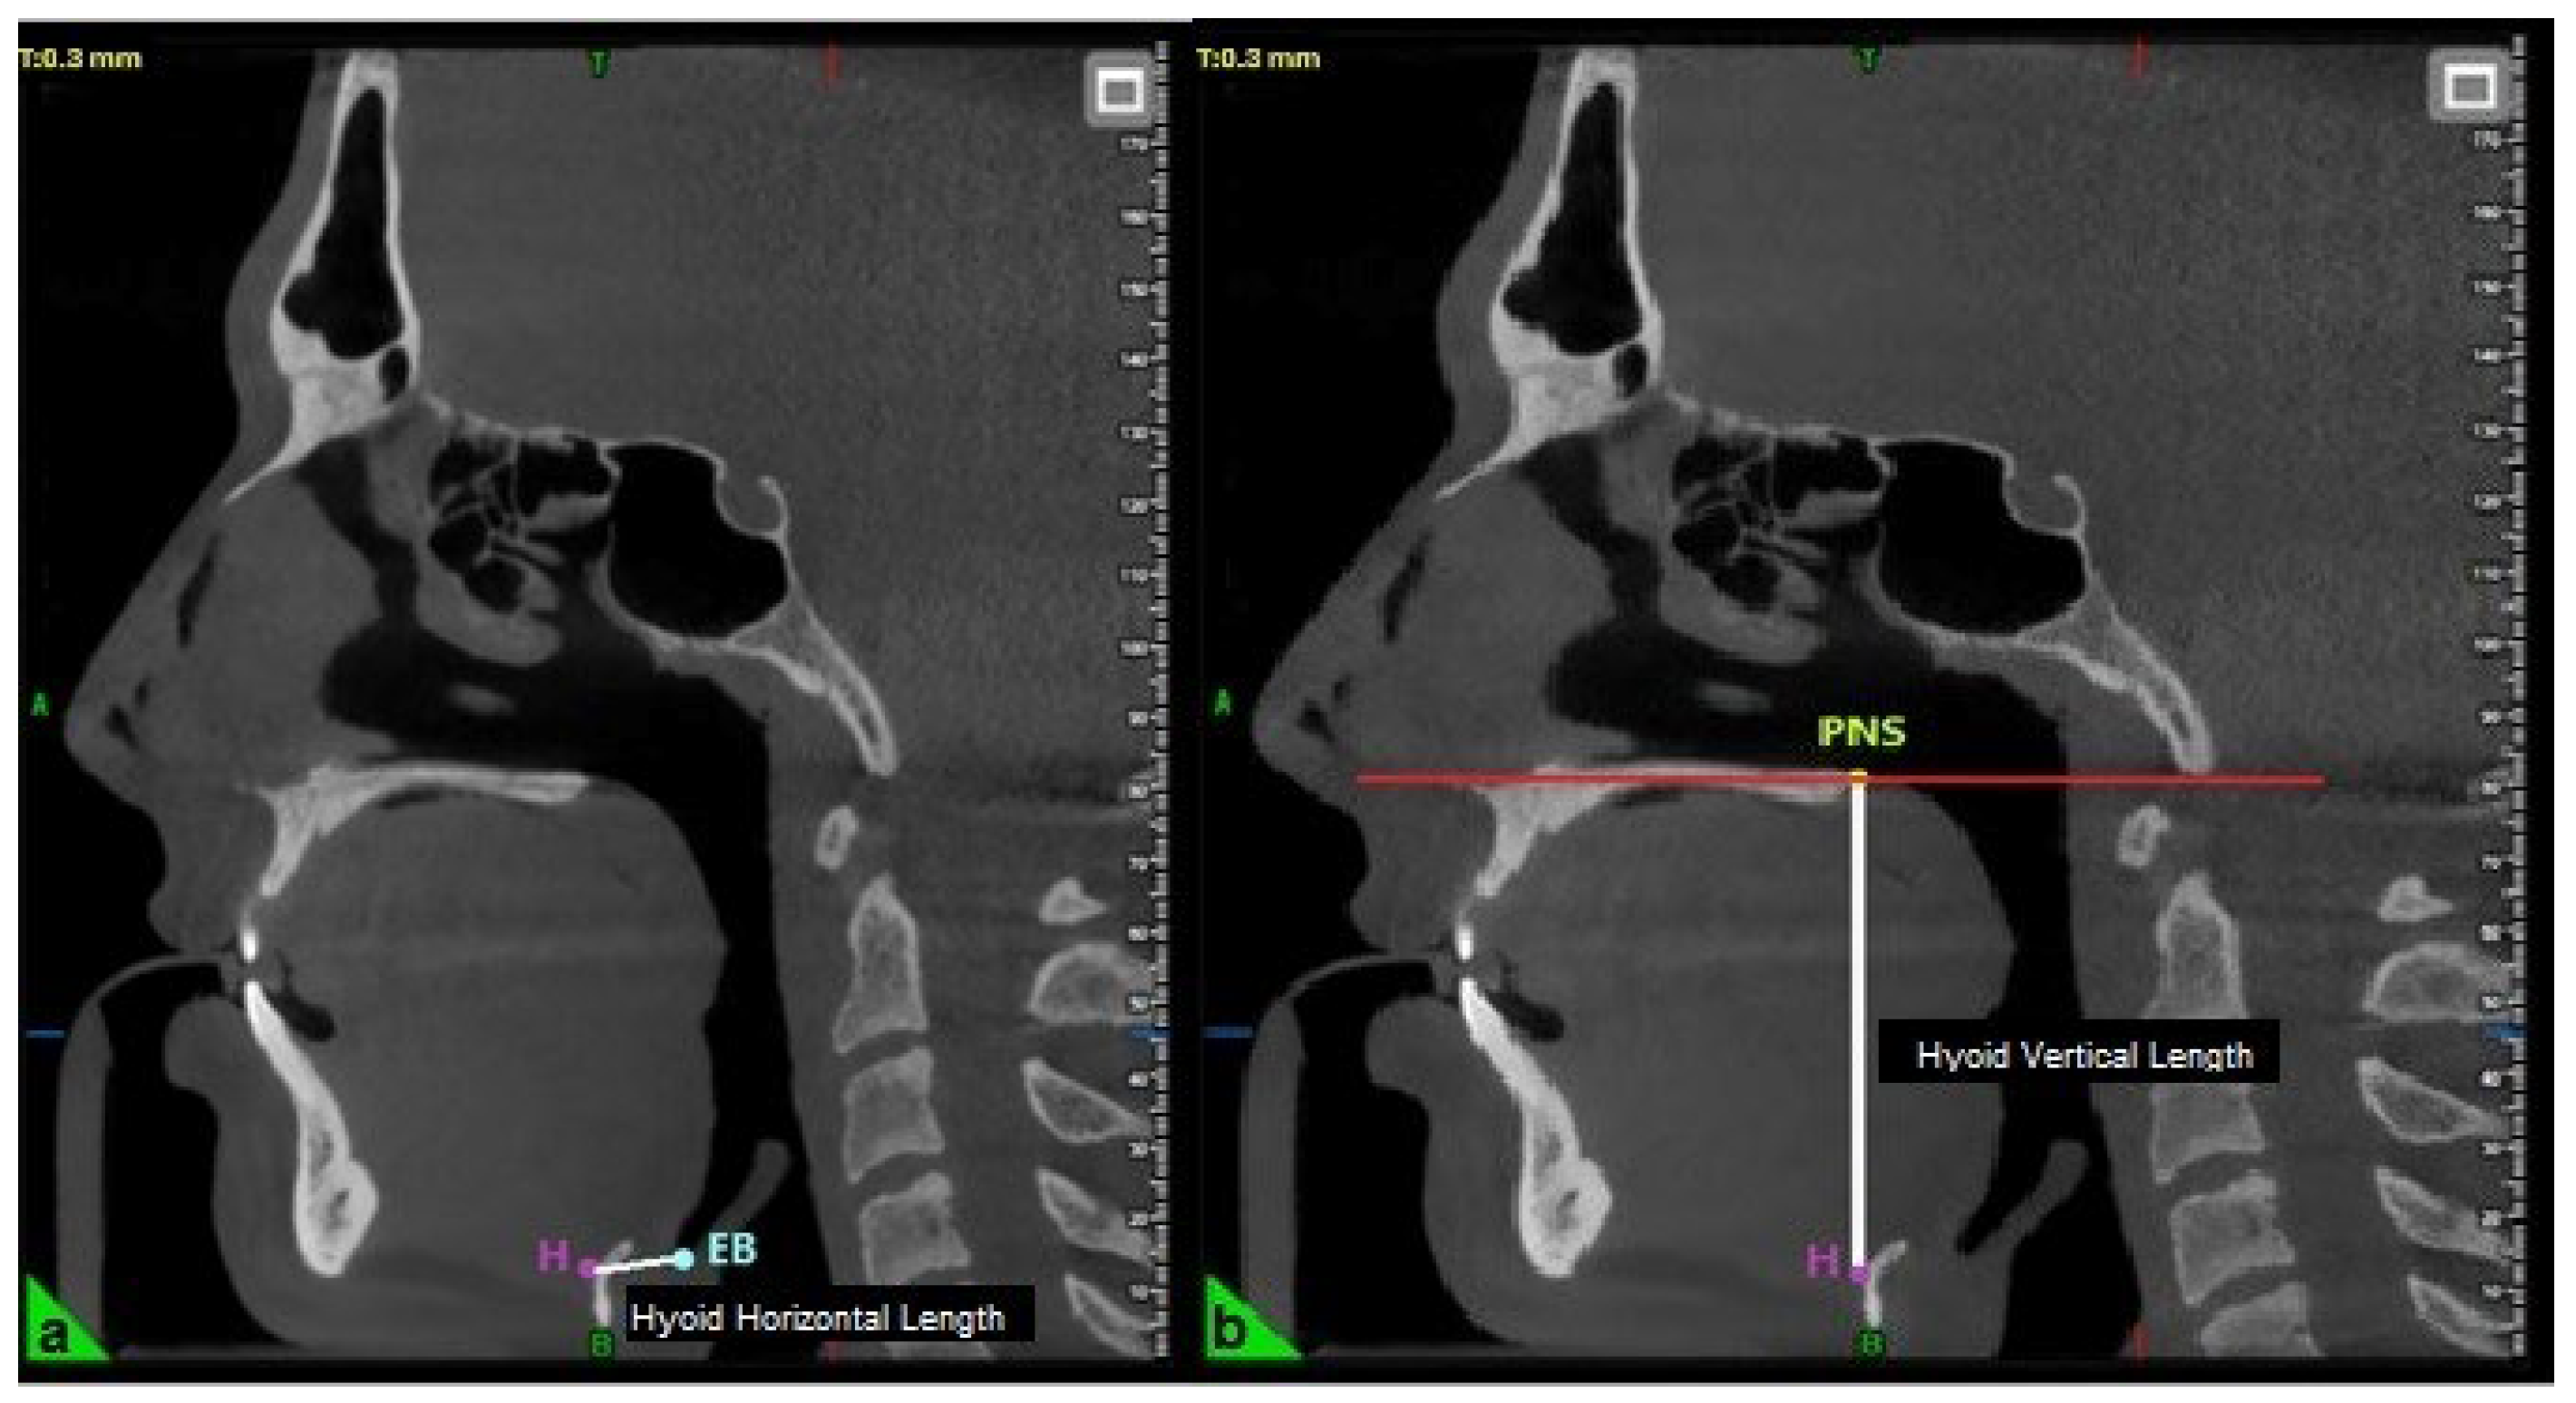

2.7. Three-Dimensional Cephalometric Measurements

| Hyoid Horizontal Length (mm) | 14.08 ± 3.08 |

| Hyoid Vertical Length (mm) | 62.87 ± 8.14 |